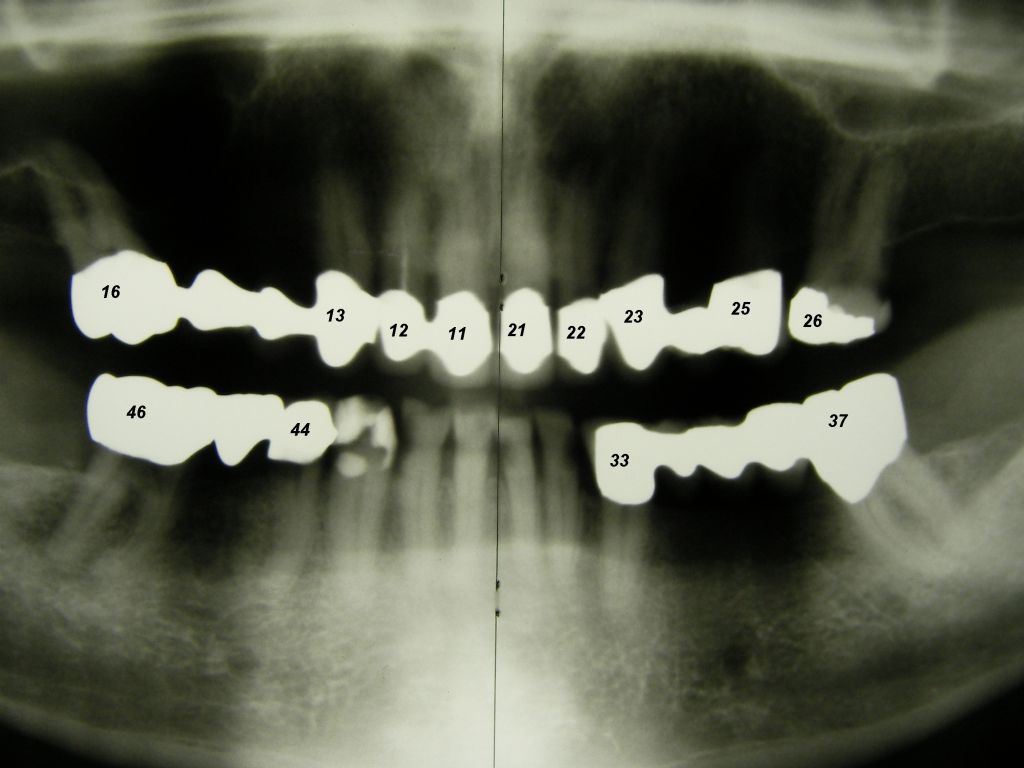

Das etwas dunkle Röntgenbild links(6/2003) zeigt diverse Probleme. Hier interessiert, daß der Zahn 22 (sprich: "zwei", "zwei") am 28.10.05 Schmerzen bereitete, weil der Zahnnerv unter Eiterbildung abgestorben war. Es brauchte 3 medikamentöse Einlagen, bis der Zahn ruhig war und am 18.11.05 eine Wurzelfüllung und einen Titanstift in den Wurzelkanal bekommen konnte. Bei der anschließenden Röntgenkontrolle rechts fiel der schlechte Randschluß der Krone 22 auf.

Weil auch die anderen Schneidezahnkronen (12-22) durch Randreparaturen und den schlechten Randschluß erneuerungsbedürftig aussahen, wurden 4 Einzelkronen geplant. Vorher hieß es aber noch, die schlechte Wurzelfüllung im Zahn 12 (Röntgenbild links) besser zu machen. Hierfür wurden am 17.2.06 die alten Kronen 11 und 12 entfernt. Rechts das Bild nach Entfernung von alten Füllungen und Karies.